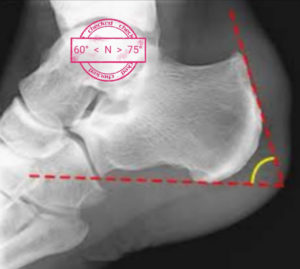

<p>Il semble nécessaire de mesurer et d’évaluer la verticalisation du calcanéum et/ou l&#8217;importance de la proéminence (l&#8217;angle de Fowler et Philip, l&#8217;angle de Chauvaux et Liet) par rapport à l&#8217;insertion du tendon d&#8217;Achille.</p>

<p><img decoding="async" src="https://commentposeruntape.fr/wp-content/uploads/2020/04/Screenshot_20200329_140806-300x269.jpg" alt="maladie de haglund" width="300" height="269" class="size-medium wp-image-34109 aligncenter" srcset="https://commentposeruntape.fr/wp-content/uploads/2020/04/Screenshot_20200329_140806-300x269.jpg 300w, https://commentposeruntape.fr/wp-content/uploads/2020/04/Screenshot_20200329_140806.jpg 600w" sizes="(max-width: 300px) 100vw, 300px" /></p>

<p style="text-align: center;">La &#8220;normalité&#8221; se situe entre un angle de 60° et 75</p>